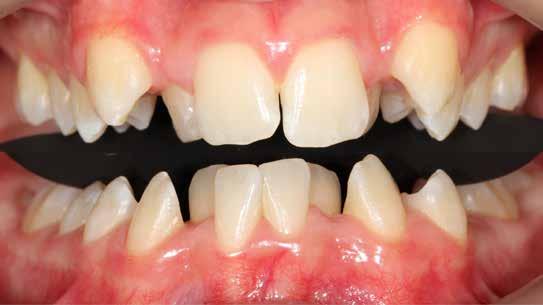

Ebben a cikkben egy 16 éves lánypáciens esetét szeretném bemutatni (1–7. képek)

Mint sok páciensem, akiknél végül nincs szükség állcsontműtétre, ők is megjárták a saját „kálváriájukat”: már több fogszabályozó kollégánál jártak, és mindegyik azt mondta nekik, hogy állcsontműtét nélkül az eset nem megoldható.

Végső elkeseredésükben időpontot foglaltak hozzám, és legnagyobb örömükre egyértelműen látszódott, hogy a Pitts Protokollok-kal nincs szükség az orthognáth műtétes beavatkozásra.